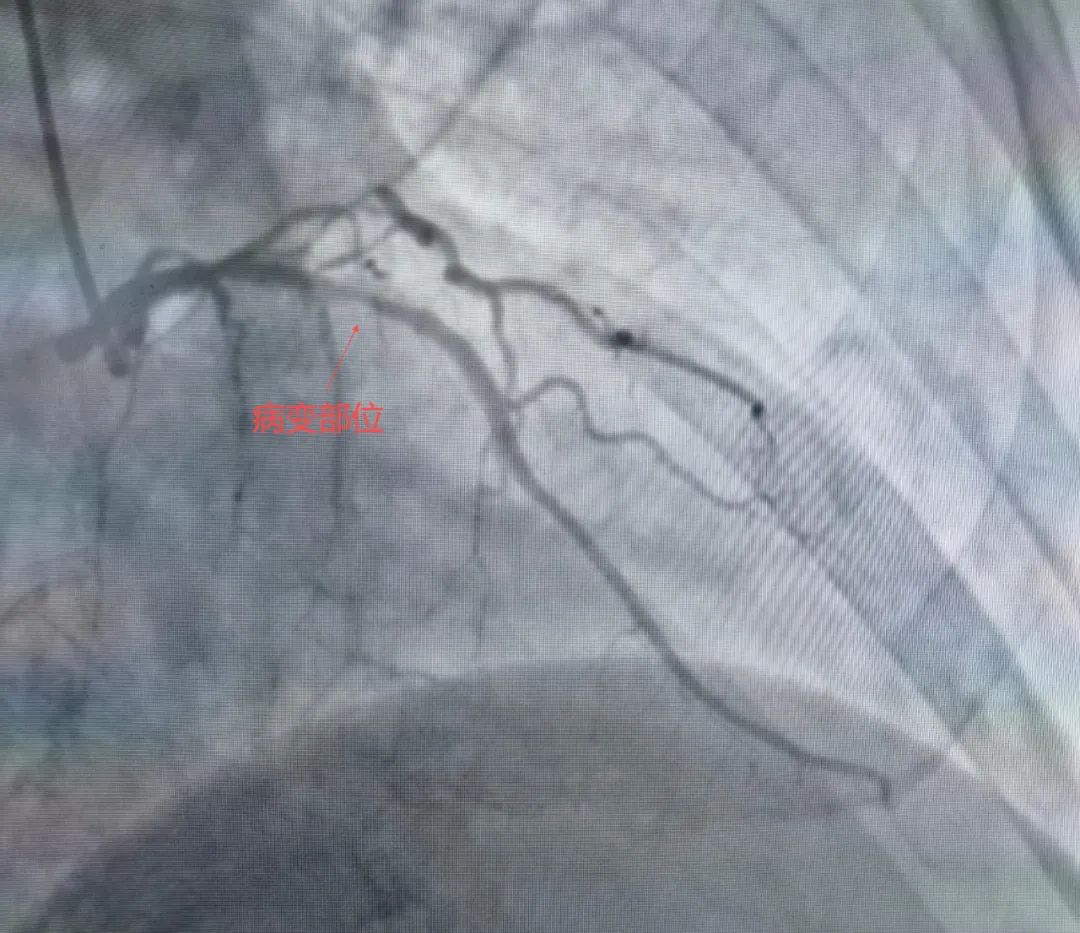

65岁的赵大爷因反复胸闷胸痛入院,冠状动脉造影显示其前降支近段存在重度钙化狭窄,血管钙化程度评分达III级(Nakamura分级),管腔狭窄超过90%。此类病变如同血管内“顽石”,常规介入器械难以通过,传统球囊扩张术无法使血管充分扩张,极易导致夹层等风险,手术难度和风险极高。

针对赵大爷的复杂病情,团队进行了充分术前讨论,决定采用“冠状动脉旋磨+冲击波球囊”的组合方案,最终成功置入支架,整个手术过程顺利,免除了患者外科开胸搭桥的痛苦。